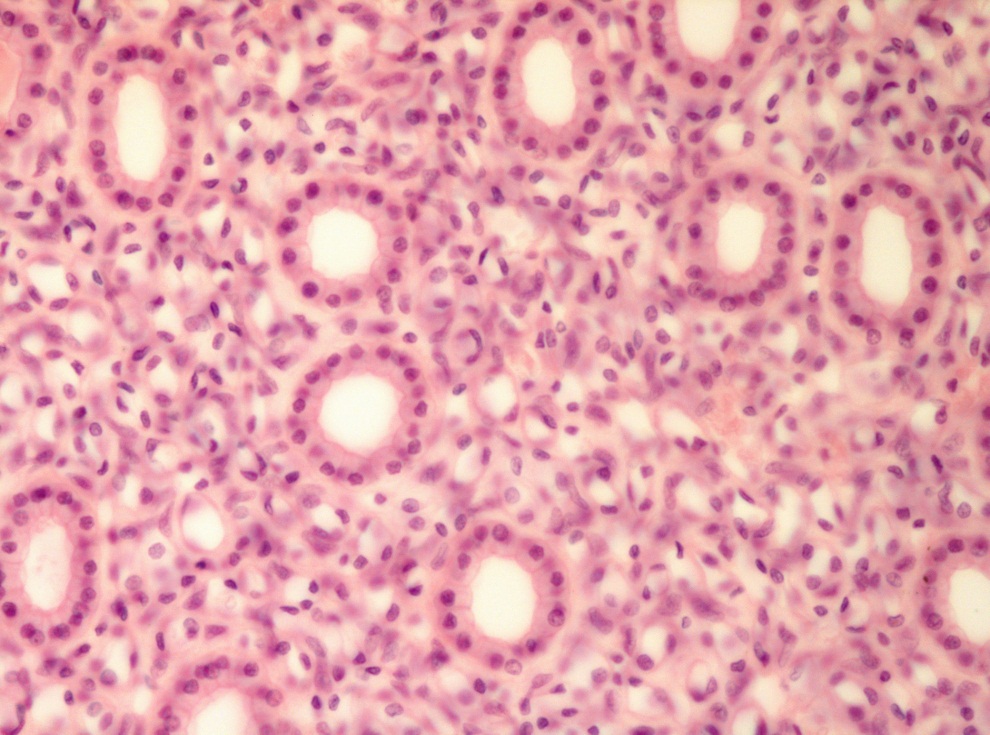

Однослойный однорядный кубический эпителий. Почка.

Окраска гематоксилином и эозином.

Ядро клетки

Базальная мембрана

Подлежащая соединительная ткань

Базальный полюс клетки

Апикальный полюс клетки

Просвет канальца